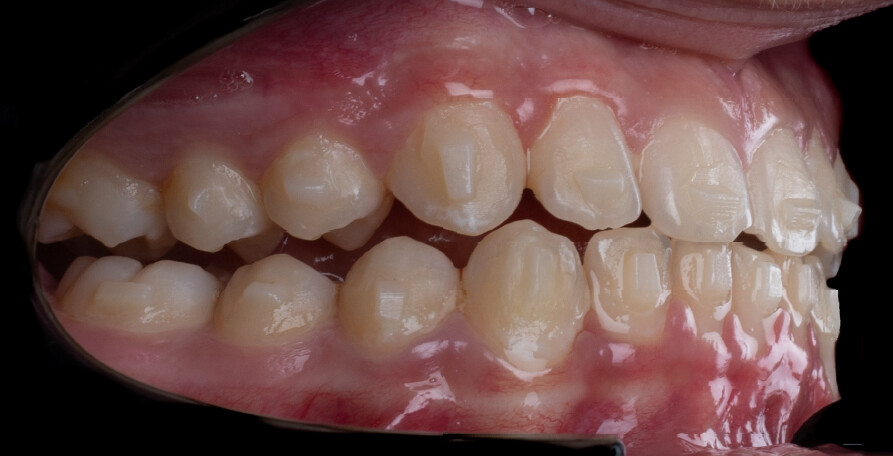

The treatment was carried out using Angel Aligner clear aligners, with strict adherence to periodontal biological limits. Both maxillary incisor intrusion and transverse expansion were carefully monitored throughout the process to prevent any periodontal compromise. Mandibular advancement was initiated directly from the 4th aligner using advancement blocks, eliminating the need for a preliminary pre-advancement phase. The patient was at the CS3 stage of cervical vertebral maturation, corresponding to the pubertal growth spurt, a biologically favorable period for condylar remodeling and skeletal adaptation. A total of 35 aligners with advancement blocks were used, followed by 10 additional aligners incorporating Class II elastics on Angel Buttons to finalize rotations and alignment. With weekly aligner changes, the overall treatment duration was approximately 45 weeks (10 months), aligning with the expected biological timeline for condylar remodeling. For mandibular anterior intrusion, the Frog Protocol combined with interproximal reduction (IPR) achieved complete leveling of the Curve of Spee.